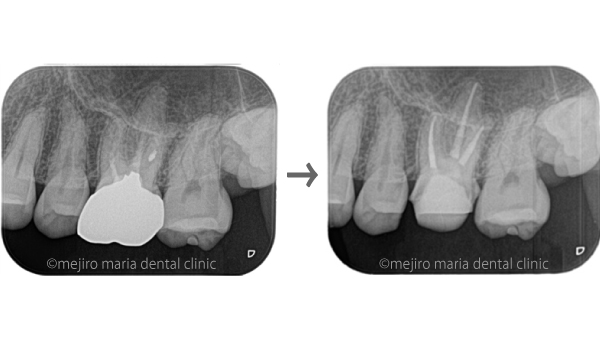

に対する、精密根管治療のアプローチ(再根管治療)_治療前後比較治療前のレントゲン画像.jpg)

に対する、精密根管治療のアプローチ(再根管治療)_治療前後比較治療後のレントゲン画像.jpg)

バイオセラミックにて根管充填を行いました。レントゲン写真からは根尖まで良好に隙間なく根管充填を行っていることが確認できます。

1回目の治療終了後、2週間後には違和感等は感じられないようにまで回復しました。

3ヶ月後に再度経過観察を行い、外科的歯内療法の必要性を判断する予定です。